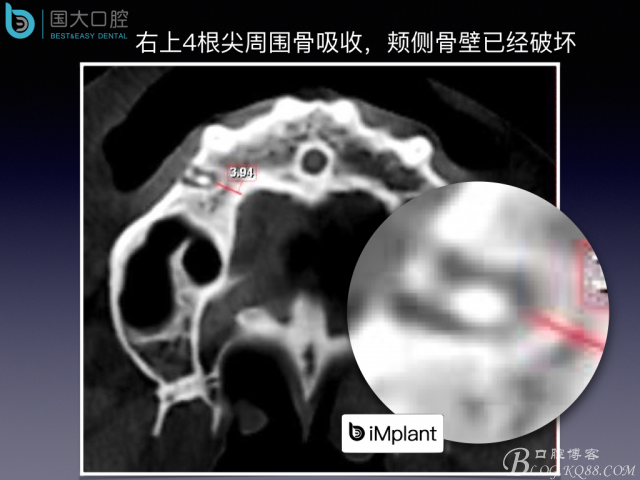

偏向顎側(cè)的即刻種植,應該如何修復?

20160820113240_88889.jpeg